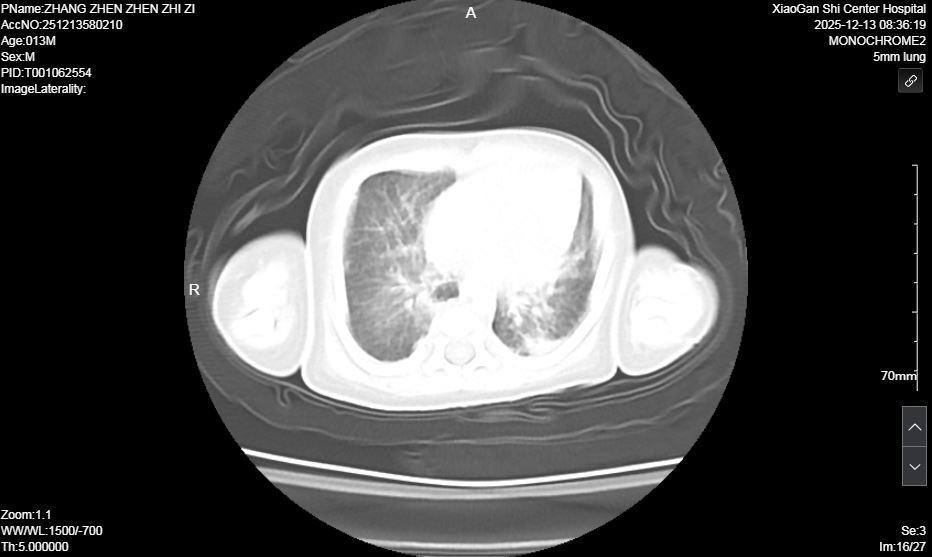

術(shù)前肺部超聲及CT均提示雙肺實(shí)變明顯